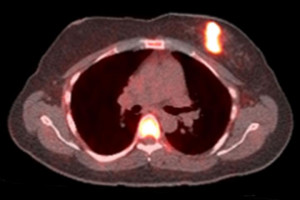

The compound, 21-[18F] fluorofuranylnorprogesterone (FFNP), attaches to progesterone receptors and can be detected with a positron emission tomogrophy (PET) scan. When more progesterone receptors are present, the PET signal is higher.

The women underwent a PET scan using FFNP, followed by three doses of oestrogen over a 24-hour period, and then a second PET scan a day after the oestrogen treatment.

For 28 women, the PET signal in the tumour increased considerably after exposure to oestrogen, indicating that their oestrogen receptors were working and had responded to the hormone by triggering an increase in progesterone receptor numbers.